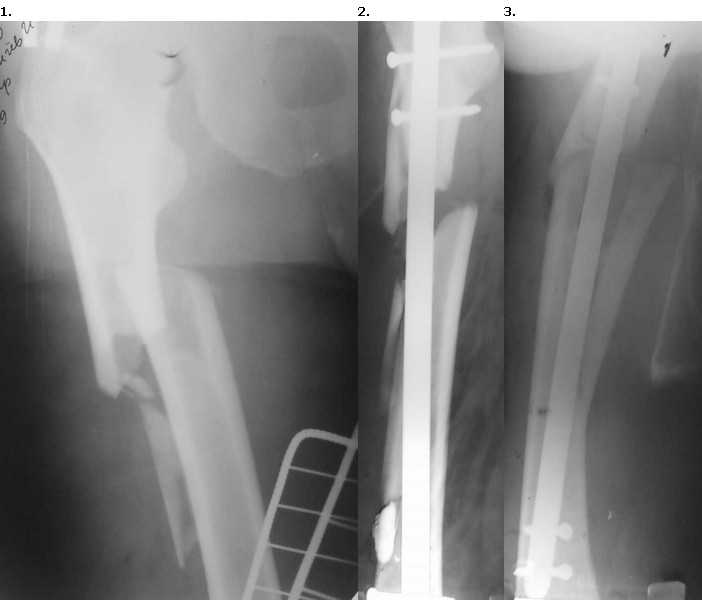

Пациент 56 лет поступил в отделение 28.12.09 со свежим переломом в/3 правого бедра. 15.01.10 произведен закрытый БИОС гвоздем Sanatmetal (d13мм), во время которого произошло раскалывание проксимального и дистального отломков. ЭОПа в больнице нет, для определения локализации направителя ползовались стареньким "Арманом". После заведения гвоздя по проводнику снимки на столе больше не делали, дистальное блокирование оч.быстро с использованием электромагнитной навигации. В послеоперационном периоде выраженные боли и отек. На контрольных рентгенограммах вот такая картина. После посмотрели за экраном - гвоздь стоит стабильно как в проксимальном, так и в дистальном отломке,но контакта между проксимальным и дистальным нет. Вопросы:

1. Что делать дальше? (По возможности бюджетно, поскольку пациент уже здорово потратился на гвоздь)

2. В какие сроки (если делать)?

3. Какие рекомендации по двигательному режиму?